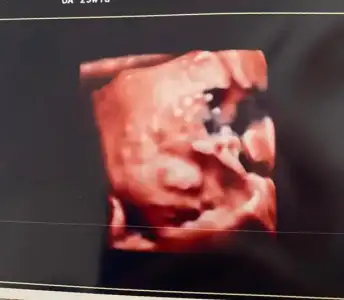

Sonbahardagel Sonbahardagel Z zerdecalim Teach_Mavi Teach_Mavi Melikeben Melikeben dr alttan bakti bi suruntu aldi akinti bu dedi dönemsel olabilir diyerek fitil verdi 1 hafta sonra tekrar gelmemi istedi cok sagolun kizlar dun gece gece aksiyon yasadik bebek suyu gayet yerindeymis 1.350 gr 38 cm olmus 🙏🙏🙏🙏

Eklentiler

• IMG-20230619-WA0002.webp

IMG-20230619-WA0002.webp

10,1 KB · Görüntüleme: 74